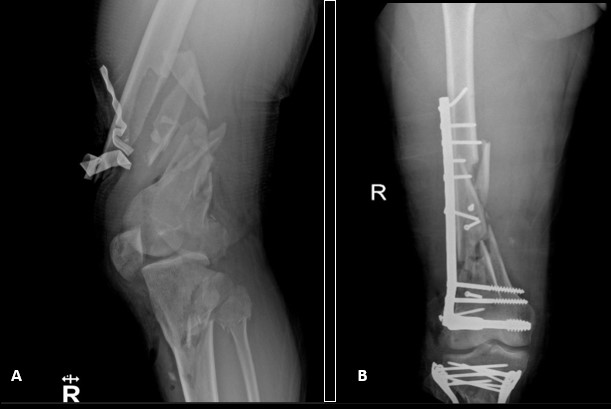

Initial treatment will be defined according to the hemodynamical stability of the patient and the severity of trauma. According to the classification, some actions could be taken. For example, open fractures, vascular injuries, joint dislocations and/or femoral neck fractures should always be prioritized and early definitive stabilization or a temporal stabilization with external fixators under the concept of damage control could be performed.

The definitive stabilization of long bone fractures in the first 24 hours positively impacts survival1,21-23. Hemodynamically stable patients should undergo definitive fixation of fractures during the first surgery (Figura 3). However, prolonged interventions (over 90 minutes) in hemodynamically unstable patients are associated with unfavorable outcomes. Furthermore, major surgery can trigger and increase immune response resulting in a clinical condition called “Second Trauma” 15,17,24. Therefore, delayed definitive stabilization has been implemented in hemodynamically unstable patients to reduce the effect of the second trauma 25,26. These patients should undergo damage control with a temporary fixation, followed by physiologic stabilization and a deferred definitive fixation in a second surgical time 5 to 10 days after damage control (Figura 4) 10,16,27,28.